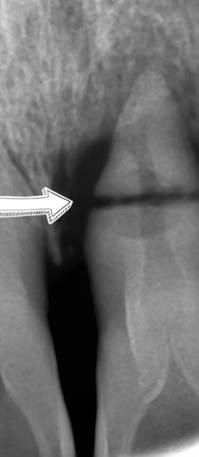

많이 흔들리는 치아들은 엑스레이 상에서 치아뼈가 많이 녹아있어 치아뿌리를 거의 잡아주지 못하고 있었구요

치아를 부딪히는 사고도 당하셨다고 합니다.

자세히 보는 정밀 엑스레이를 찍어봤더니

치아 뿌리가 가로로 부서진 것을 볼 수 있었습니다.

당연히 흔들릴 수 밖에 없겠죠.